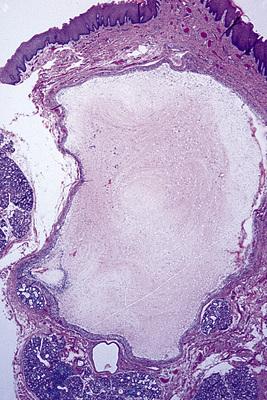

Mucin-filled cystlike cavity beneath the mucosal surface. Minor salivary glands are present below and lateral to the spilled mucin.

mucocele

High-power view showing spilled mucin that is associated with granulation tissue containing foamy histiocytes.

mucocele

- Low-power photomicrograph showing a cyst below the mucosal surface.

- High-power view of cystic cavity lined by thin cuboidal epithelium. Adjacent to the cyst is an excretory salivary gland duct lined by columnar epithelium.